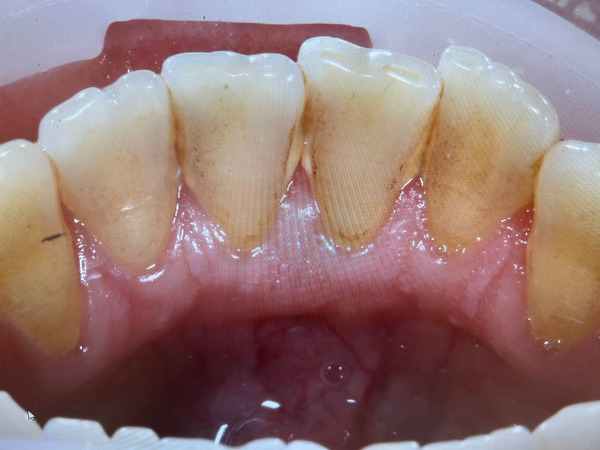

А так выглядит сигаретный налёт на зубах курильщика. Почувствуйте разницу.

Потемнение эмали. Это самый яркий, так сказать, бросающийся в глаза признак постоянного курения. В стоматологии для этого придумали даже специальный термин «никотиновые зубы». Характерный жёлтый цвет зубов плохо поддаётся профессиональной чистке, особенно, если личная гигиена у человека хромает и он редко посещает стоматолога. Этот тёмный налёт курильщика образуется в несколько стадий:

- Сначала из-за разницы температуры горячего (40–60ᵒС) сигаретного дыма и вдыхаемого воздуха на поверхности эмали образуются микротрещины, в которые проникают табачные смолы.

- Затем на поверхности зубов курящего образуется смоляная плёнка, под которой накапливается патогенная микрофлора, образующая зубной камень такого же тёмного цвета.